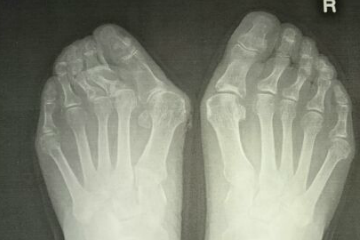

外反母趾は症状、変形、疼痛の痛みの具合は様々です。

外反母趾の問題は疼痛(とうつう)、痛みだけではありません。

・外反母趾の変形症状による身体を支える機能の低下、消失